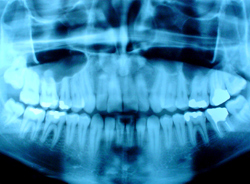

口腔外科

また交通事故やスポーツなどの外傷、顎変形症ならびに唾液腺疾患などの外科的疾患のほかにも、口腔粘膜疾患、神経性疾患、口臭症などの内科的疾患も含まれます。

口腔に異常があると、食事や発音・会話がうまくできなくなったり、見た目に対する障害も現れます。治療により口腔・顎・顔面全体の自然な形態や機能が回復すると、顔全体がいきいきとし、健康的な美しさを取り戻すことができます。そのお手伝いをするのが口腔外科です。